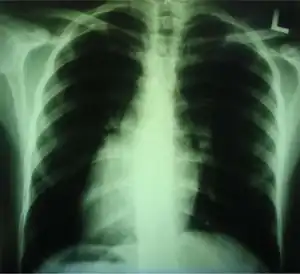

Medical diagnosis of the two forms of congenital dextrocardia can be made by ECG[3] or imaging.